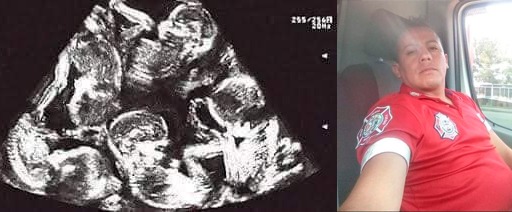

Esto está muy lejos de ser un simple embarazo múltiple: La esposa de un bombero de #Ixtapaluca Estado de México dará a luz a 13 bebés, informó durante la sesión de cabildo el regidor de Morena, Gerardo Guerrero, quien pidió a sus compañeros otorgar un apoyo económico a la familia, pues actualmente ya tienen seis hijos aparte de los 13 que pronto nacerán.

«Hay un compañero que trabaja en esta administración, concretamente en el área de bomberos, Antonio Soriano Ordóñez, él está casado con la ciudadana Maritza Hernández, son ciudadanos de aquí de Ixtapaluca. En 2017 tuvieron a su primer bebé, en el 2020 tuvieron gemelas, en el 2021 tuvieron trillizas, hasta ahí llevamos seis», relató. «En próximos días esta pareja va tener 13 hijos más, lo dije bien, 13 hijos más, con estos 13 van a tener 19», expuso el regidor ante los otros integrantes del cabildo ixtapaluquense.

Felipe Arvizu, presidente municipal en Ixtapaluca, Estado de México, confirmó el acontecimiento y dijo que se espera que el nacimiento de los 13 bebés sea atendido en el Hospital ISSEMYM de Toluca, Estado de México, debido a la complejidad del alumbramiento. La madre y los 13 bebés se encuentran en buenas condiciones de salud pues están siendo monitoreados permanentemente.

Maritza Hernández, esposa del bombero de Ixtapaluca Antonio Soriano y madre de los 13 bebés, podría romper un récord Guinness al ser la única mujer en el mundo en parir a 13 niños a la vez.